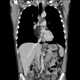

Pericardial lipoma